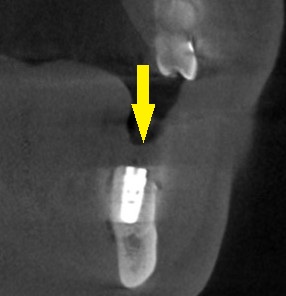

3か月ほどして、CTを撮影してみると、下の写真2段目のように、大きく骨欠損となっていました。

2本のインプラント埋入を目指したいのですが、2本目の部位では、下方に通っている神経までの距離は3~4mm程度でした。